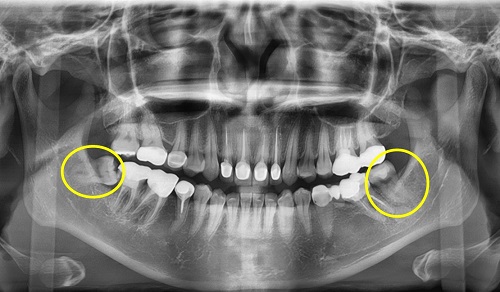

치과 치료를 하면 알 수 있는 것이 치아는 함부로 뽑지 않습니다. 정말 최대한 살려보고 그래도 안 되면 뽑아서 임플란트 등으로 빈자리를 채웁니다. 사랑니는 다른 치아들과 달리 발치를 해야 할 때도 있습니다. 잘 자란 사랑니는 특별한 문제를 일으키지 않아 뽑지 않아도 됩니다. 하지만 대부분의 사랑니는 말썽을 부립니다. 출혈, 염증, 통증 및 악취, 충치 들 여러 가지 문제를 일으킬 확률이 높기 때문에 뽑아야 합니다.